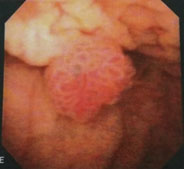

大変申し訳ありませんが例を上げるために画像を供覧致します。

画像1は膀胱内部に突出して膀胱腫瘍であり黒い部分が溜まった尿です。黒い部分が少ないと膀胱の壁が分厚くなる事で発見出来ない可能性が高くなります。前立腺の評価も膀胱内の尿が溜まっている事で正確な前立腺の体積を評価する事が可能となります (画像1、2)。

画像1:膀胱腫瘍

以下超音波と同様に画像の例を提示させていただいております。

画像3:膀胱腫瘍